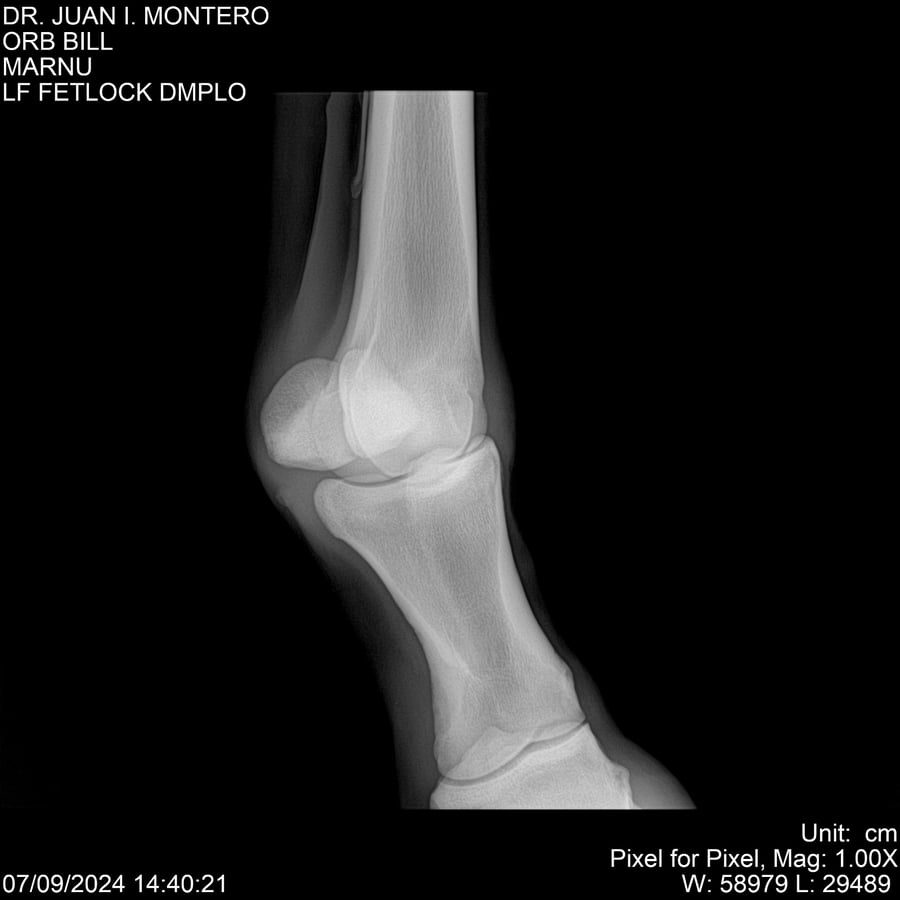

LOTE 7, ORB BILL 🔥 🔥 🔥 Lote Anterior Volver al remate Lote Siguiente Ficha Contacto Montevideo - Ficha del Lote Identificador: #282523 Categoría: Yeguarizos Montevideo - 83 Visualizaciones ClicData Contacto Empresa: Abelenda N. R., Walter Hugo Nombre*: Teléfono* : E-mail* : Mensaje Enviar Registrese gratis Este contenido Exclusivo está disponible sólo para usuarios registrados Ingresar